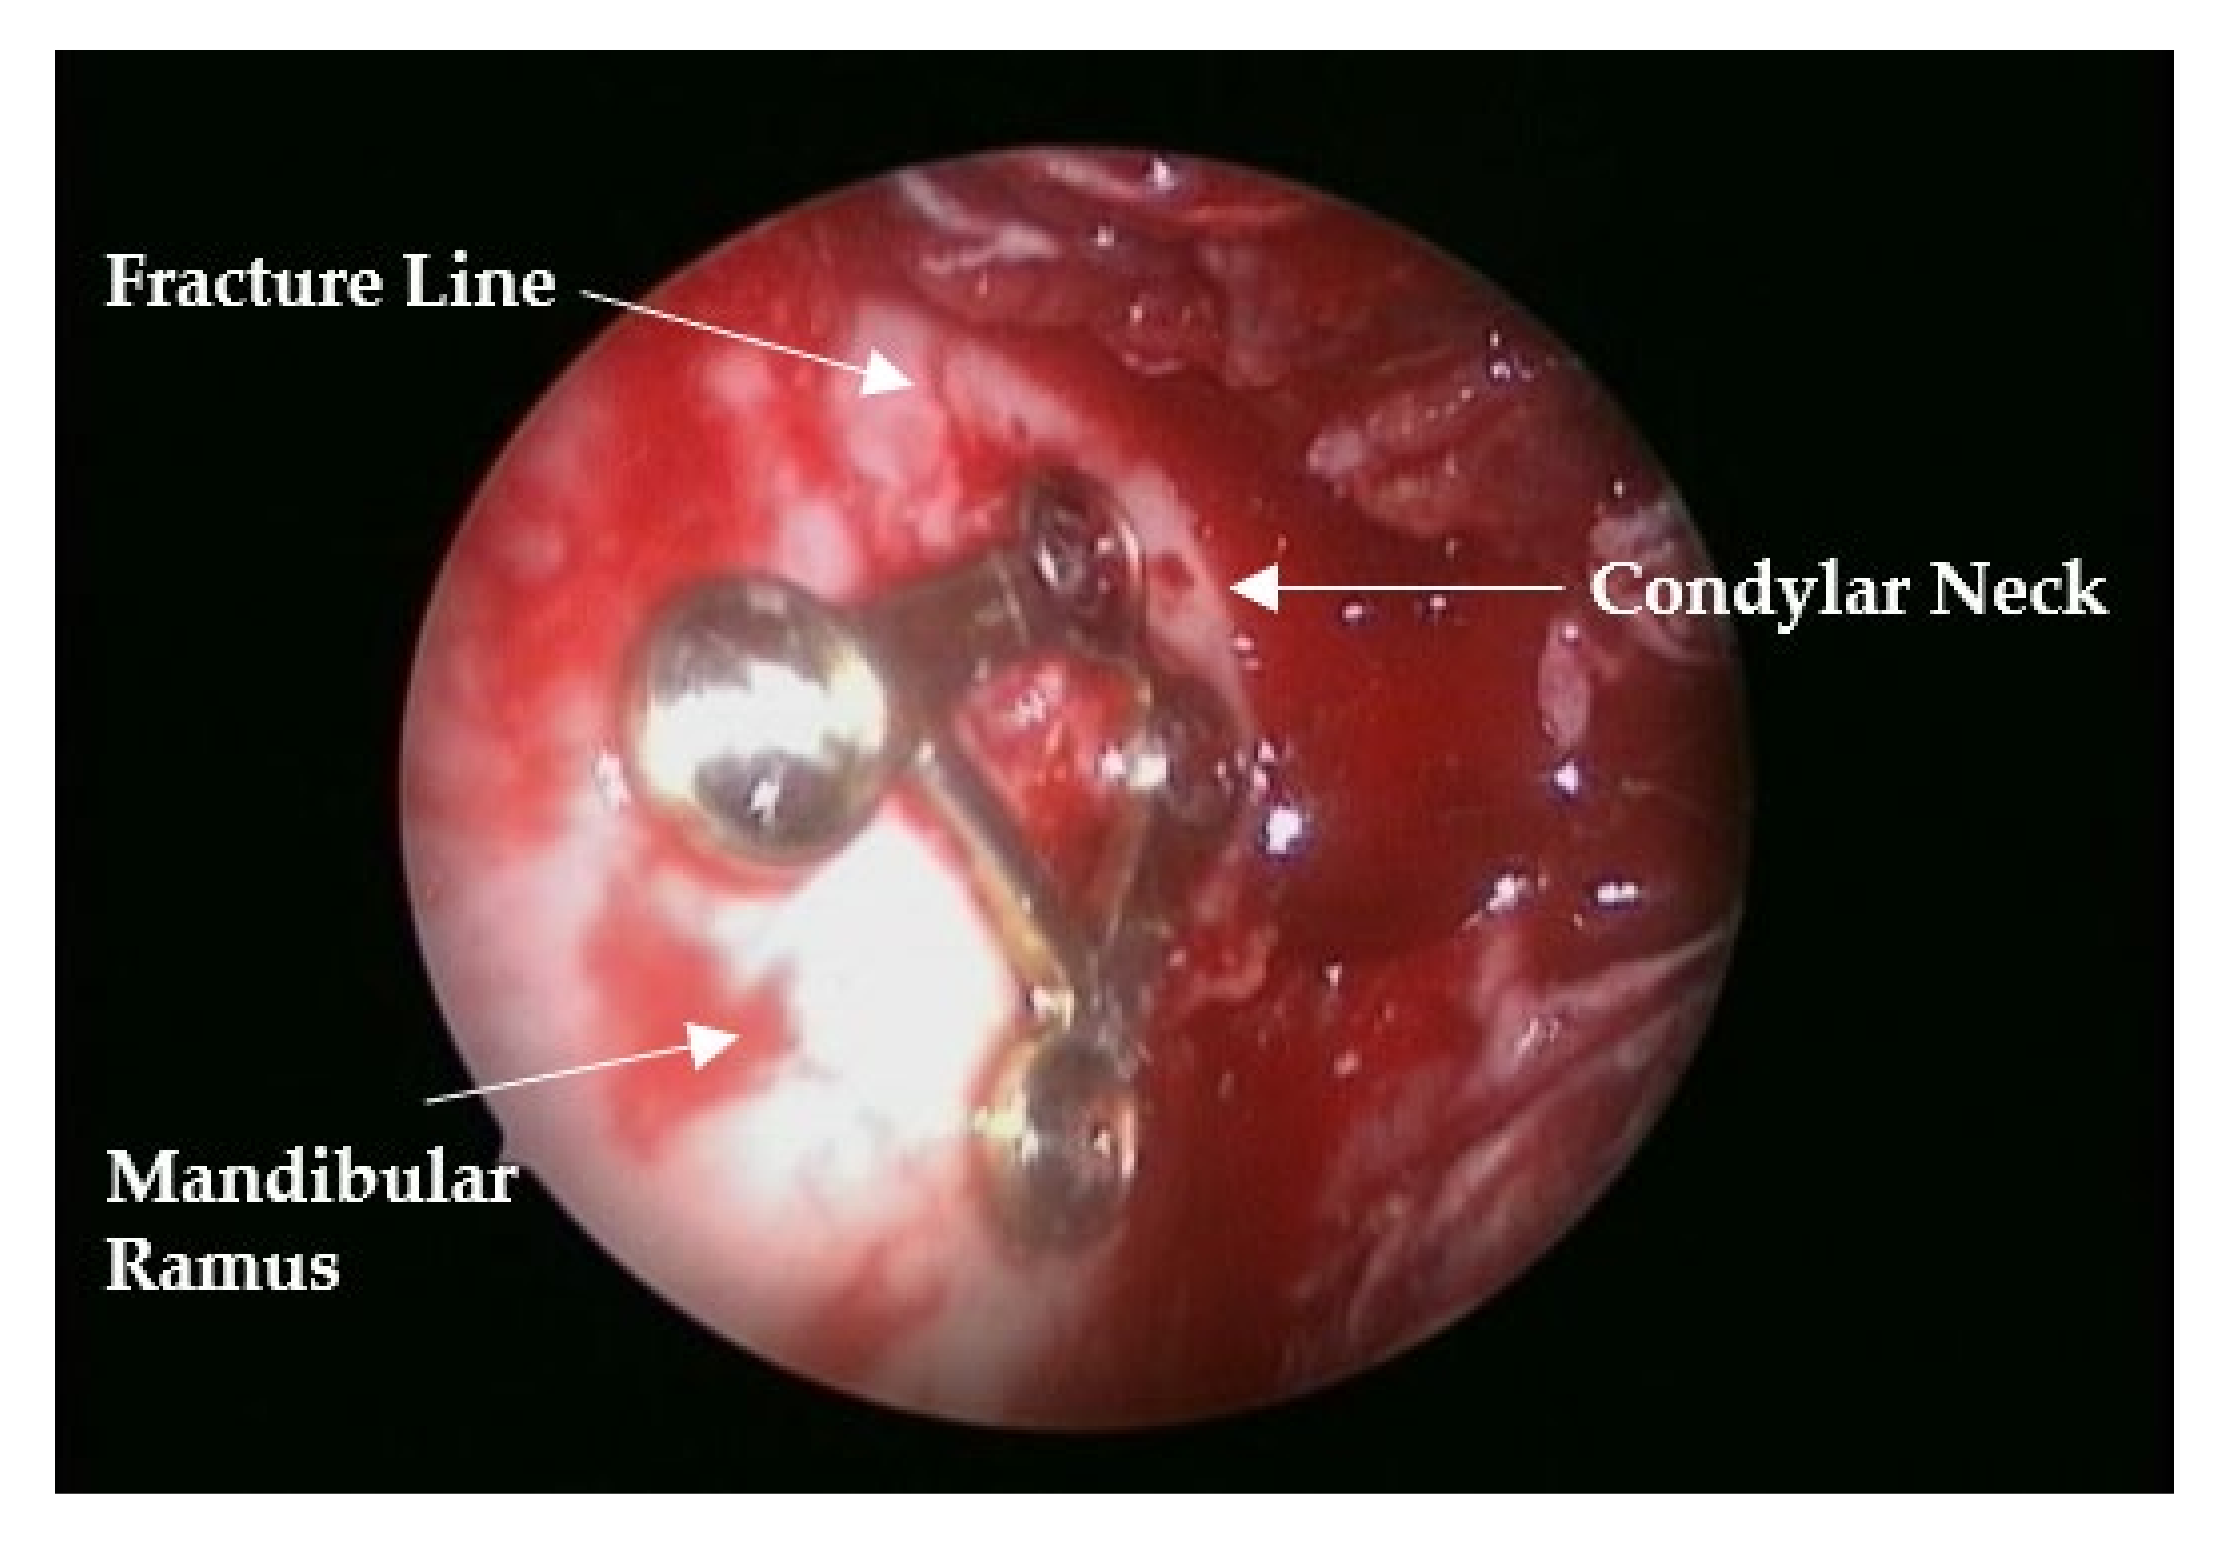

Reliability of a Trapezium Miniplate with Endoscope-Assisted Internal Fixation in Mandibular Subcondylar Fractures: A Three-Dimensional Analysis

2. Materials and Methods